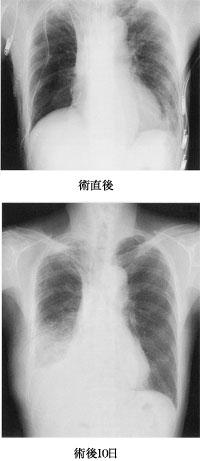

72歳の男性。右下葉肺癌の手術後、嗄声が出現した。術後3日目から食事が開始され、病棟内の歩行が許可された。術後10日目に発熱し、禁食となった。術後12日目に解熱し、作業療法が開始された。術直後と術後10日目の胸部X線写真を別に示す。この患者への対応で優先すべきなのはどれか。